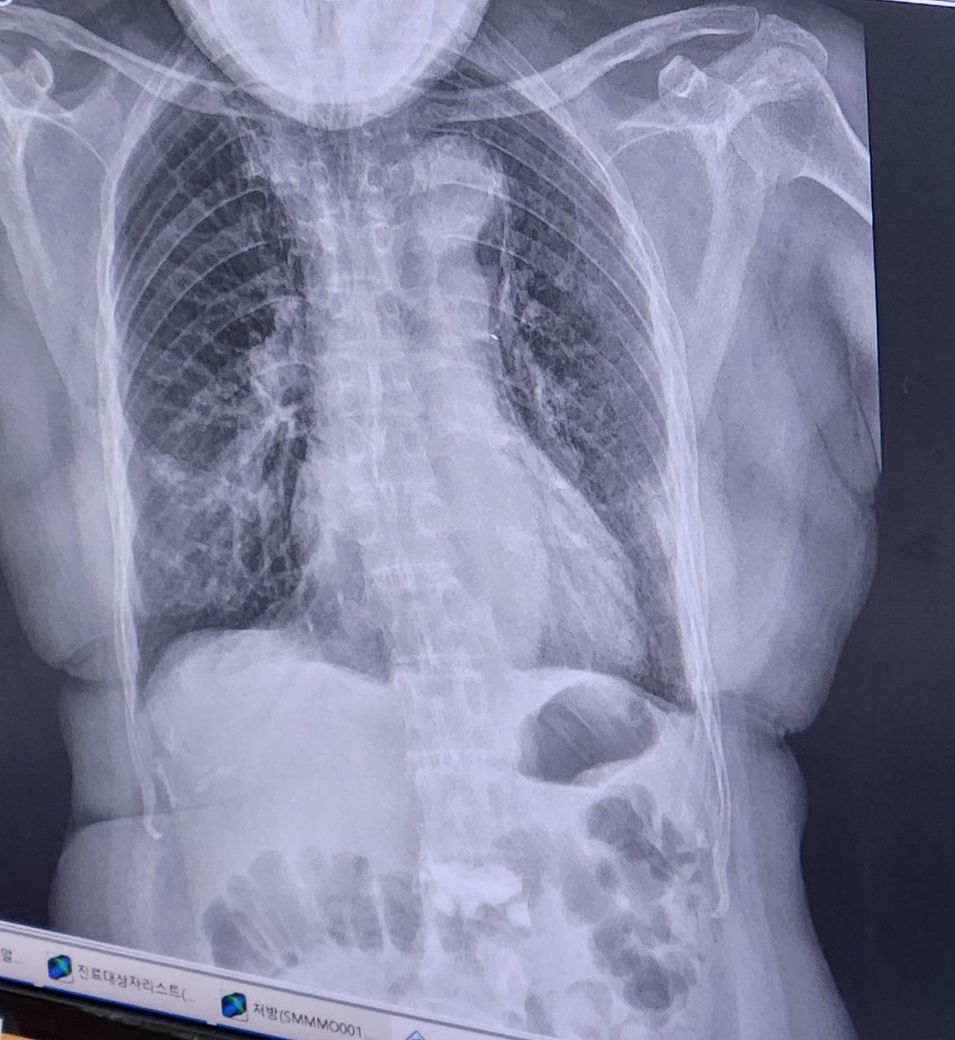

일주일전 찍은사진과 일주일후사진입니다.

궁금합니다. 위사진이 일주전 아래가 일주후 입니다

가래 색의 변화(초록색 → 연노랑색)는 염증이 줄어들면서 가래의 농도가 옅어지는 과정일 가능성이 높습니다. 초록색 가래는 보통 세균 감염이 활발한 시기에 나타나며, 연노랑색 가래는 염증이 줄어드는 과정일 수 있습니다. 하지만 정확한 폐렴의 진행 상태를 판단하려면 엑스레이 변화뿐만 아니라 혈액 검사(CRP, 백혈구 수치 등)나 산소포화도 등을 종합적으로 평가해야 합니다.

추가적인 진료나 검사가 필요할 수도 있으므로 주치의와 상의하는 것이 좋습니다